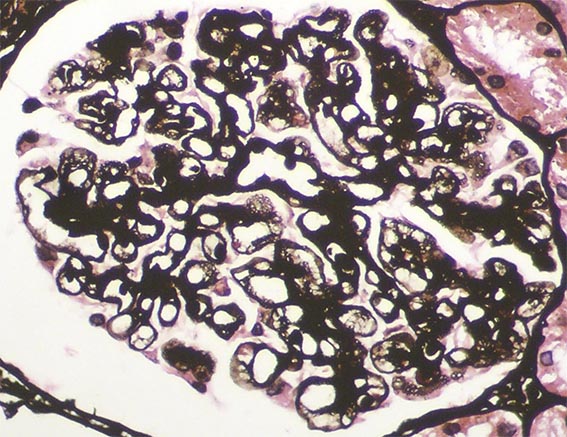

Figure 7. Methenamine-silver, X400.

Figure 8. Methenamine-silver, X400.